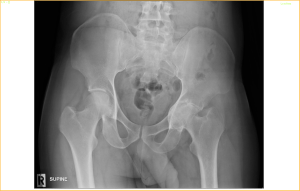

This X-ray of the Pelvis belongs to a 33-year-old man. He was diagnosed to have Rheumatoid Arthritis 2 years ago but was not managed properly. He was only treated with steroids and pain killers by many doctors. He came to see me with pain over the left hip and inability to walk properly over the last few months. This X-ray shows a severe destruction of the left hip-joint with eroded acetabulum, making the hip-joint to protrude into the pelvis. We call this condition as Petrusio acetabulum.

I feel sad for this man as nothing much can be done for the damage that has already occurred. A difficult total hip replacement is possible but he is too young for this to be done unless the pain is unbearable.